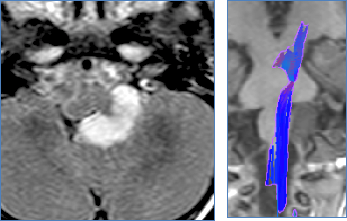

低级别胶质瘤是中枢神经系统内胶质细胞癌性生长的亚型,其特点是生长缓慢且恶性程度相对较低。尽管其侵袭性较低,但这些肿瘤仍可通过压迫周围神经和血管结构而引起显著的神经系统症状...